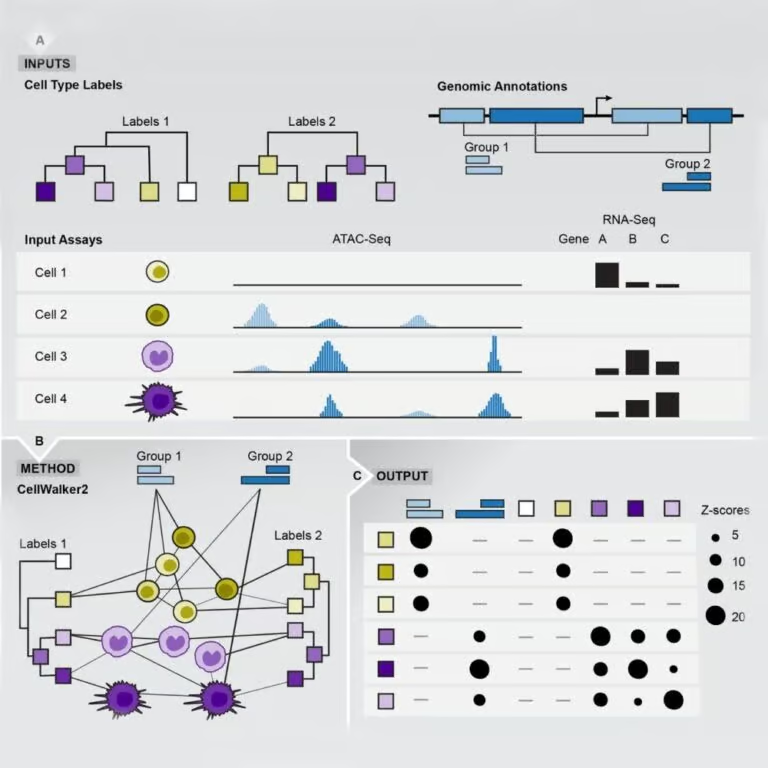

On May 22, 2025, Gladstone scientists unveiled a powerful computation tool that integrates different forms of biological data…